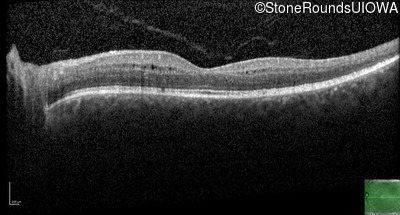

Optical Coherence Tomography - Right - 20/25 -1

Exemplar / OCT Stack